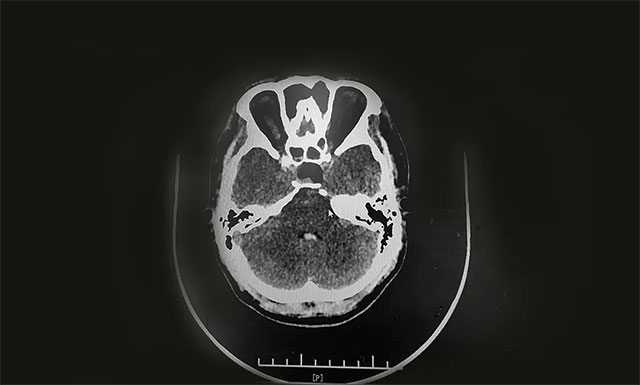

術(shù)中,在蔡司顯微鏡(雙熒光)下,見(jiàn)黃白色腫物,質(zhì)韌,其外有包膜覆蓋。李士其教授在充分保護(hù)好海綿竇、頸內(nèi)動(dòng)脈、視神經(jīng)等結(jié)構(gòu)前提下,將鞍內(nèi)可見(jiàn)腫瘤順利切除,腫瘤大小約2.5cm*1.5cm*1.5cm,并留取腫瘤送檢病理。手術(shù)順利完成,術(shù)中只失血約20毫升。

▲ 術(shù)后CT顯示腫瘤被切除